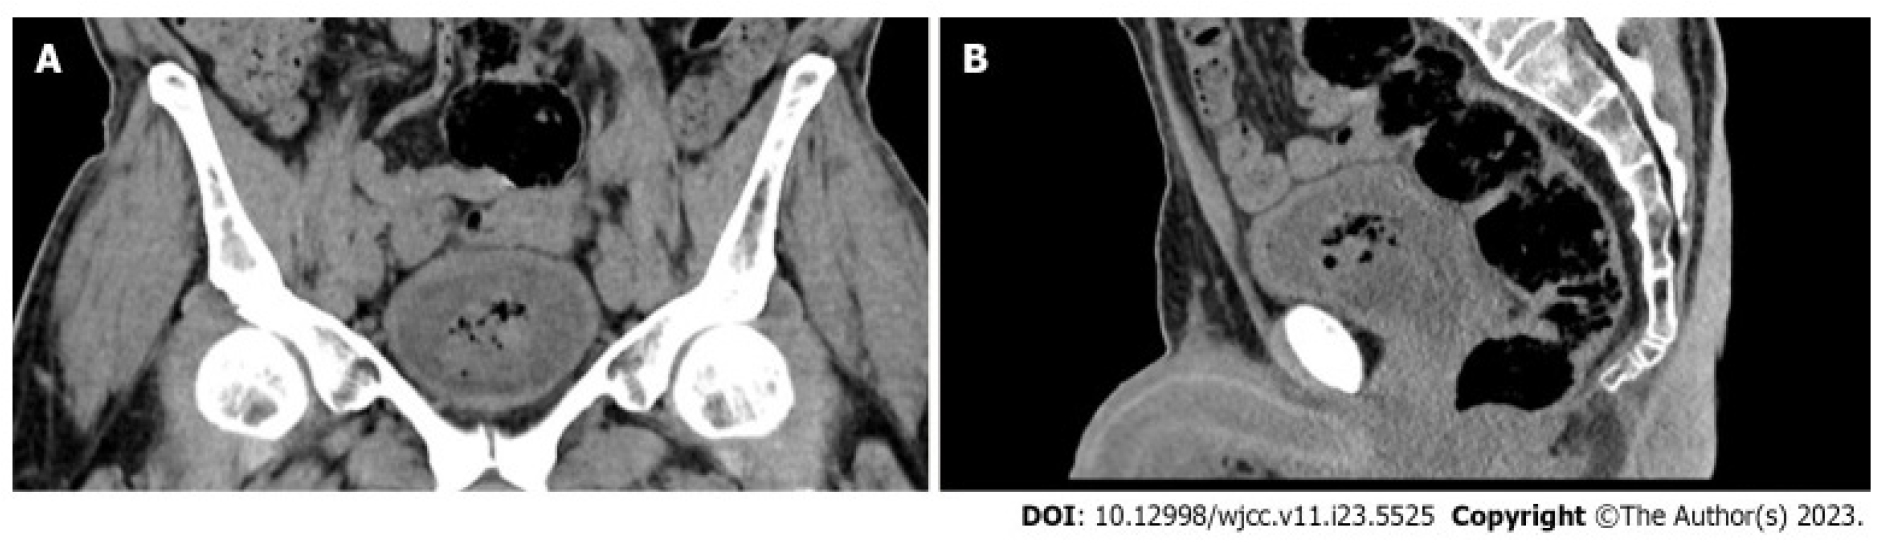

그림 3.

63세 남성 환자가 Rezūm 시술을 받은 지 2개월 후 극심한 배뇨통(dysuria), 빈뇨(frequency), 절박뇨(urgency), 간헐적 요류(interrupted stream) 증상을 호소하며 내원하였다. 검사 결과, 방광 내에 기종성(emphysematous)으로 변형된 괴사 조직이 떠 있는 상태로 발견되었고, 항생제 치료에도 반응하지 않는 세균 감염이 동반되어 있었다. 최종적으로 괴사 조직을 수술적으로 제거함으로써 치료하였다. 컴퓨터 단층촬영(CT) 영상에서 방광 내에 기종성(emphysematous) 괴사 조직이 존재함을 확인할 수 있다(Alnazari M, et al. World J Clin Cases. 2023 Aug 16;11(23):5525-5529에서 인용) [3]